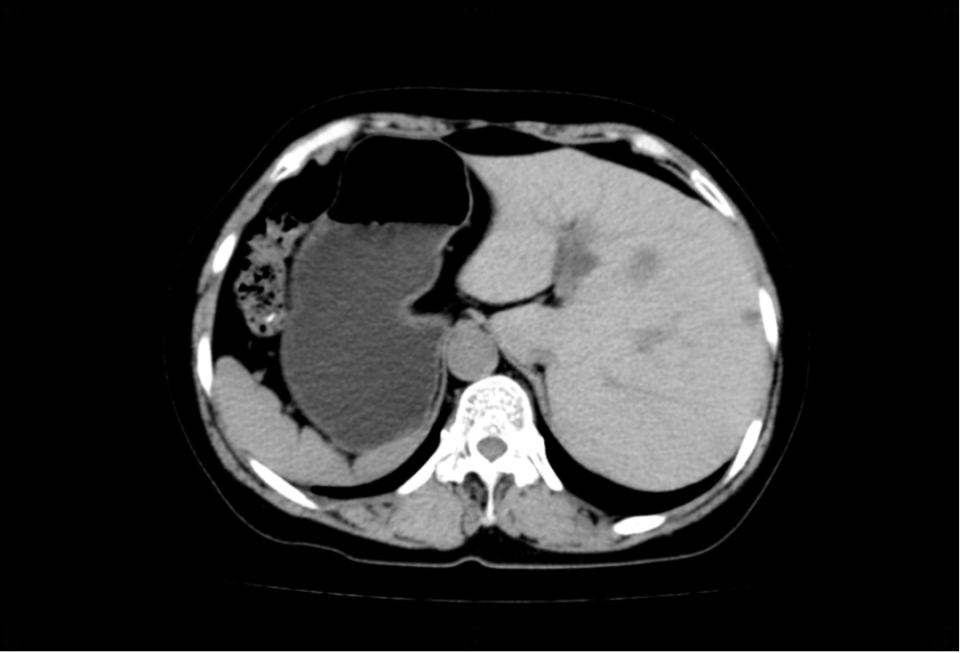

全内脏反位

什么是“全内脏反位”?简单来说,张女士的心脏、肝脏、胆囊、脾胃等所有胸腹腔器官,位置都与正常人完全左右对调。就像照镜子时看到的自己,医学上形象地称之为“镜面人”。

图片

这种先天变异的发生率极低,大约每万人中仅有1例。对于普通人来说,这只是一个有趣的医学名词;但对于即将接受手术的张女士和她的主刀医生来说,这意味着巨大的挑战。